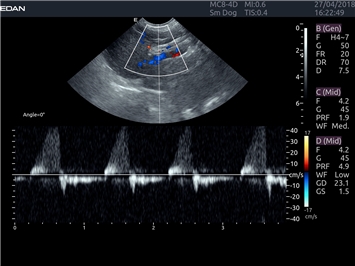

EDAN Acclarix LX4 VET

EDAN Acclarix LX4 VET представляет собой профессиональную ультразвуковую систему, специально разработанную для ветеринарных исследований. Сочетание стабильности, высокой производительности и эффективности делает эту систему идеальным выбором для современной ветеринарной практики.

Постоянно-волновой допплер:

Да

Импульсно-волновой допплер: